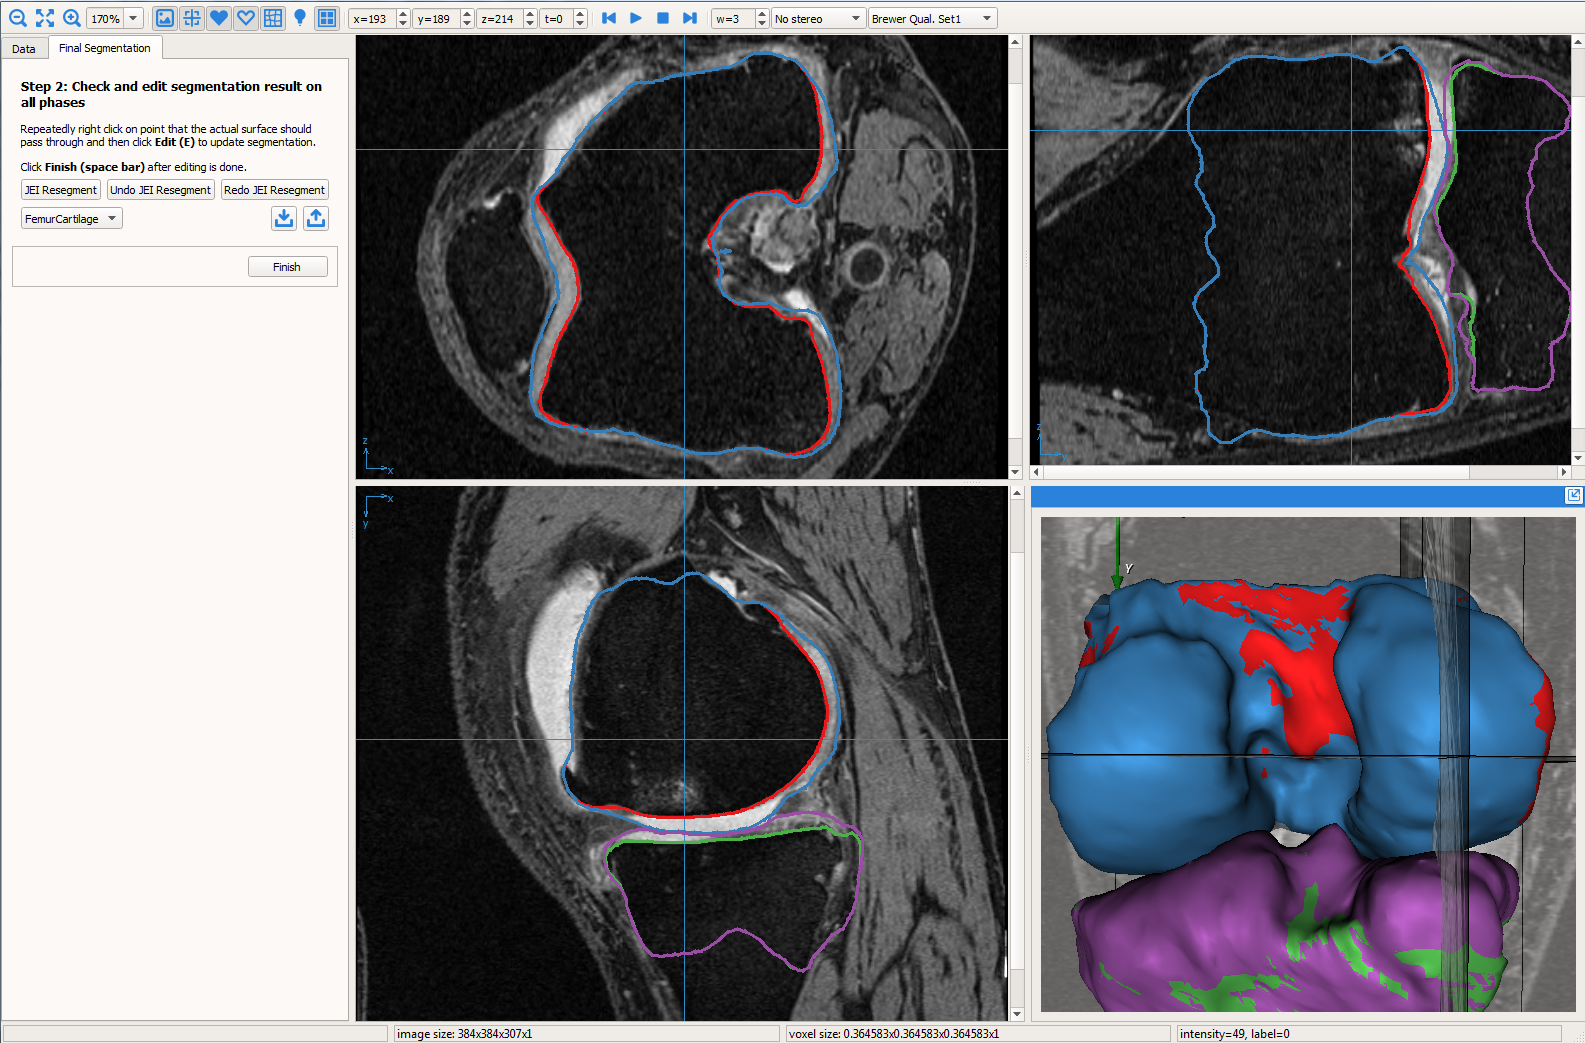

The electric lines of force (ELF) based geometric graph, image volume and residual graph were loaded into the GUI (see Fig. 1) to inspect segmentation quality and perform JEI. The work-flow is presented as a video provided in the supplementary material with an example subject with severe OA. The details of the work-flow were as follows:

User provided nudge points: The user identified correction is provided as a set of nudge points which guide the segmentation to the correct position. Fig. 3a shows the GUI magnified with the volume and the automated LOGISMOS segmentation results overlayed. The particular slice indicated is a case with severe OA having bright fluid regions improperly segmented as cartilage. The blue line with points are the nudge points indicated by the user approximately identifying the correct cartilage region.

Max-flow re-computation: Following the local graph cost modification the max-flow is recomputed in 3D within a few milliseconds and the updated surfaces rendered onto the GUI. As seen in Fig. 3b the correction made by the nudge points are reflected in the updated cartilage surface overlayed on the image volume.

The above work-flow is repeated to correct the tibial cartilage errors as well. In the intermediate steps following the correction of the femur, the tibia bone and cartilage surfaces appear to worsen. This can be attributed to a combination of the existing graph costs and the graph constraints. Since the tibia cartilage surface has no clear defined edge cost in that region, the surface result moved along with the femur corrected cartilage surface. Subsequently due to the inter-surface distance constraints between the tibial surfaces the tibial bone surface also changed. However once the nudge points provided the appropriate locations for cost modification the erroneous surfaces were corrected (Figs. 3c,d). Note that the corrections made on a single 2D slice resulted in the entire locally affected 3D neighborhood being corrected. This can be appreciated in the corresponding circled regions of the surface model.

3 Experimental Methods

MRI volumes used in this study were acquired from the osteoarthritis initiative which also had a limited number of datasets with independent standard available. All subjects were scanned using the DESS protocol with a voxel resolution of mm3. 19 baseline subjects with varying degrees of OA severity were used in this study. They were segmented using the automated LOGISMOS followed by 3D JEI correction. The geometric graph for the tibia and femur objects had 8006 and 8002 graph columns, respectively. The graph parameters used in this experiment are listed in Table 1.